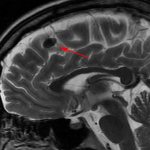

Почему развиваются органические поражения К причинам возникновения органического поражения центральной нервной системы относятся: 1.